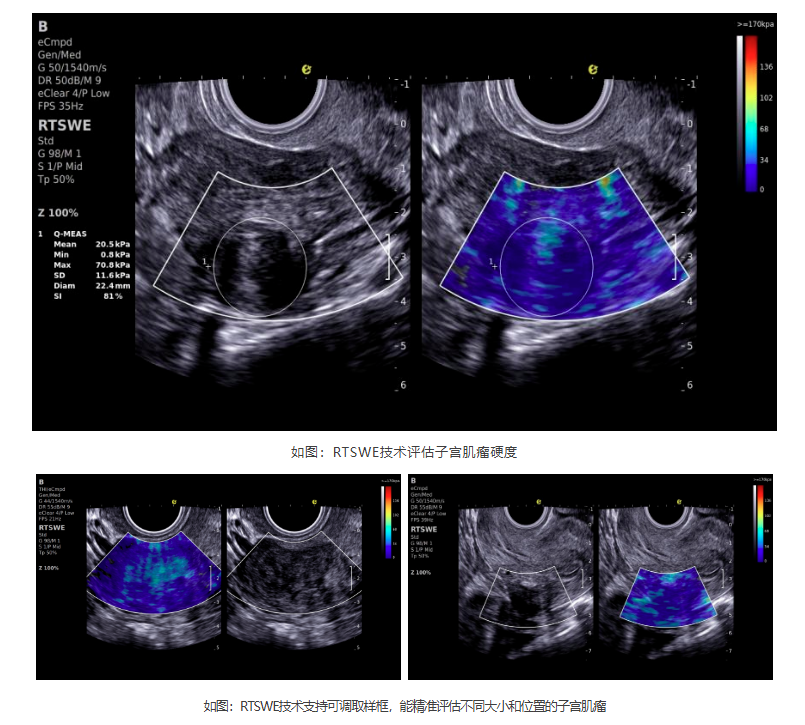

如今,hjc888黄金城官网医疗ePascal东风系列搭载的RTSWE?实时E成像技术为肌瘤良恶性的鉴别带来了突破!该技术基于OmniSound? 平面波超快速平台,以25000帧/秒的采集帧频,实现最小0.4mm病灶的精准硬度测量。它犹如为超声检查赋予"智能触诊"能力,通过定量分析组织硬度,辅助判断肌瘤性质:

cd2301cd65513af0501835669682402.png